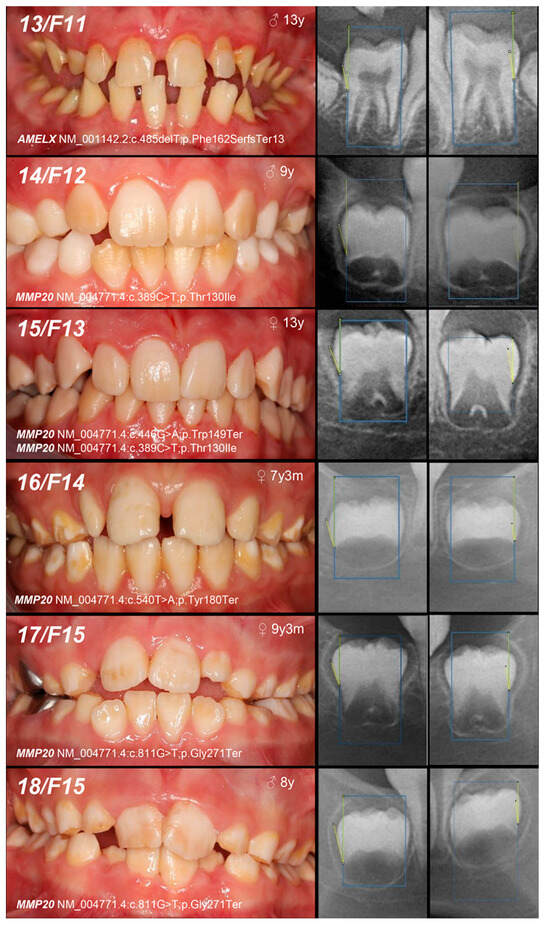

| 13, F11 | Hypoplastic (heterogeneity) | IE, XLD, AMELX | c.485delT | 0/− | p.Phe162SerfsTer13 | novel | MoS (A) Fa (NA) | likely pathogenic (PVS1:very strong, PM2:moderate) |

| 14, F12 | Hypomineralized (pigmented hypomature) | IIA2, AR, MMP20 | c.389C>T | −/− | p.Thr130Ile | [27] | MoFa (UC) | likely pathogenic (PP5: strong, PM2: moderate) GnomAD: 0.001747 |

| 15, F13 | +/− | Mo (U) Fa (NA) | ||||||

| and c.446G>A | +/− | and p.Trp149Ter | novel | likely pathogenic (PVS1:very strong, PM2:moderate) GnomAD: 0.00000398 |

| 16, F14 | Hypomineralized (pigmented hypomature) | IIA2, AR, MMP20 | c.540T>A | +/− | p.Tyr180Ter | [28] | Mo (UC) Fa (U) | likely pathogenic (PVS1: very strong, PM2: moderate) GnomAD: 0.00000707 |

| 17, 18, F15 | c.811G>T | +/− | p.Gly271Ter | novel | Mo (AC) Fa (U) | likely pathogenic (PVS1: very strong, PM2: moderate) | ||

| +/− | ||||||||

| 19, F16 | +/− | Mo (UC) Fa (U) | ||||||